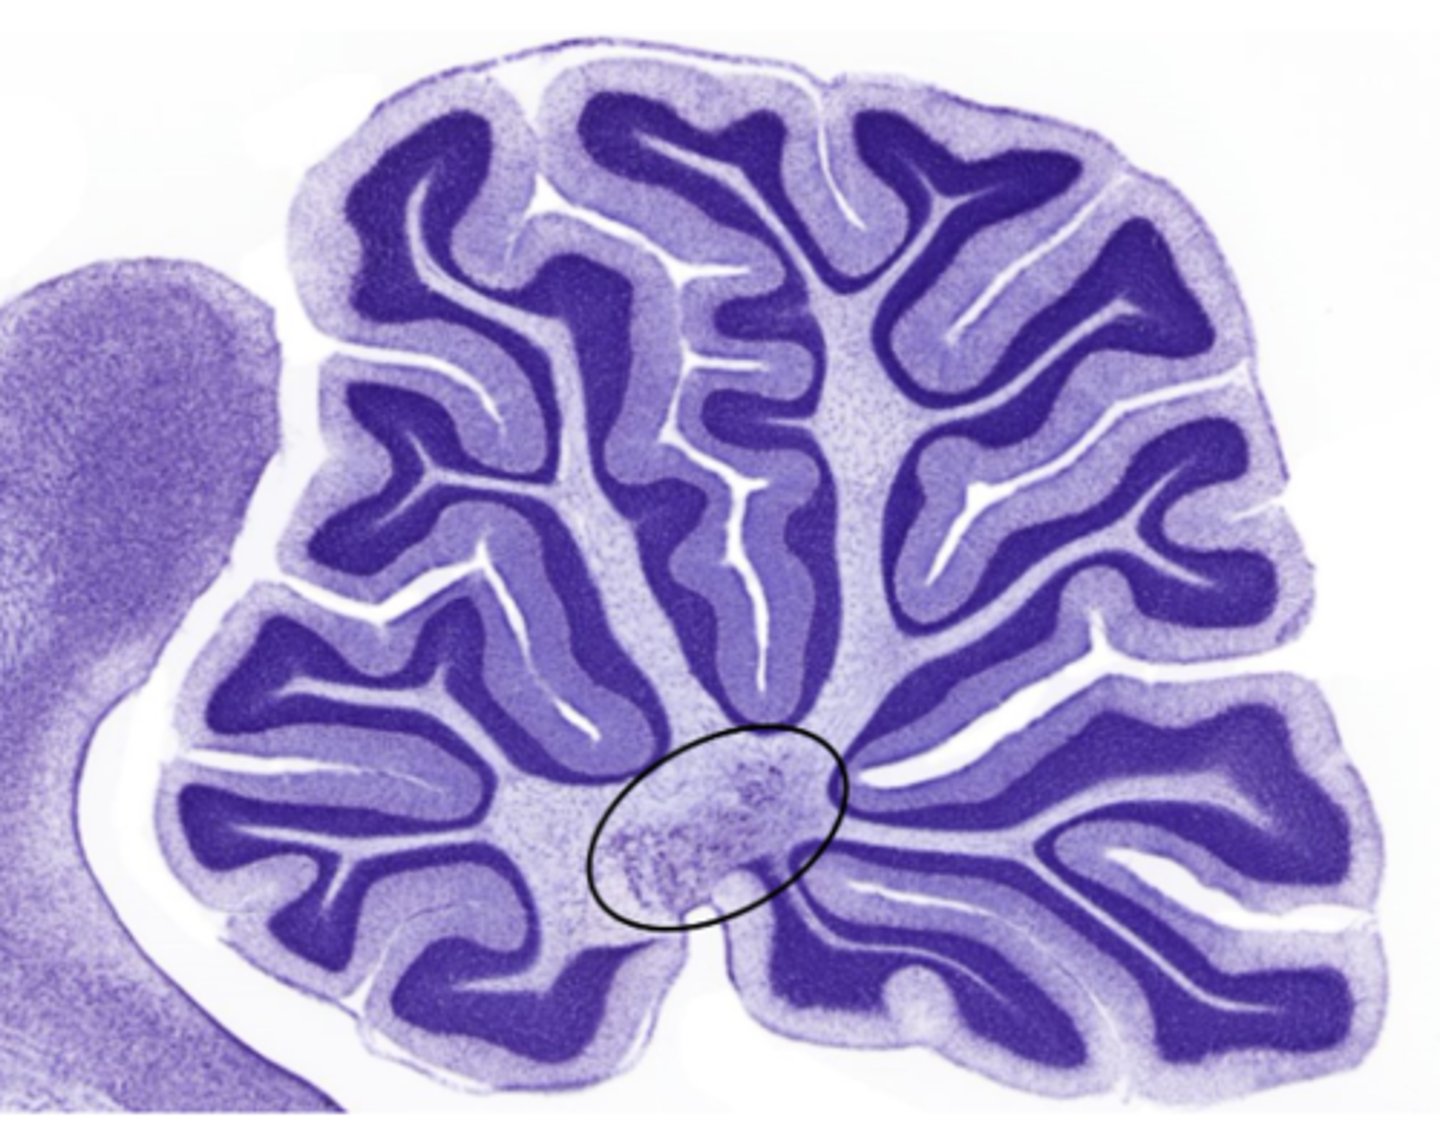

Identify the cluster of neurons circled

nucleus of the deep cerebellum